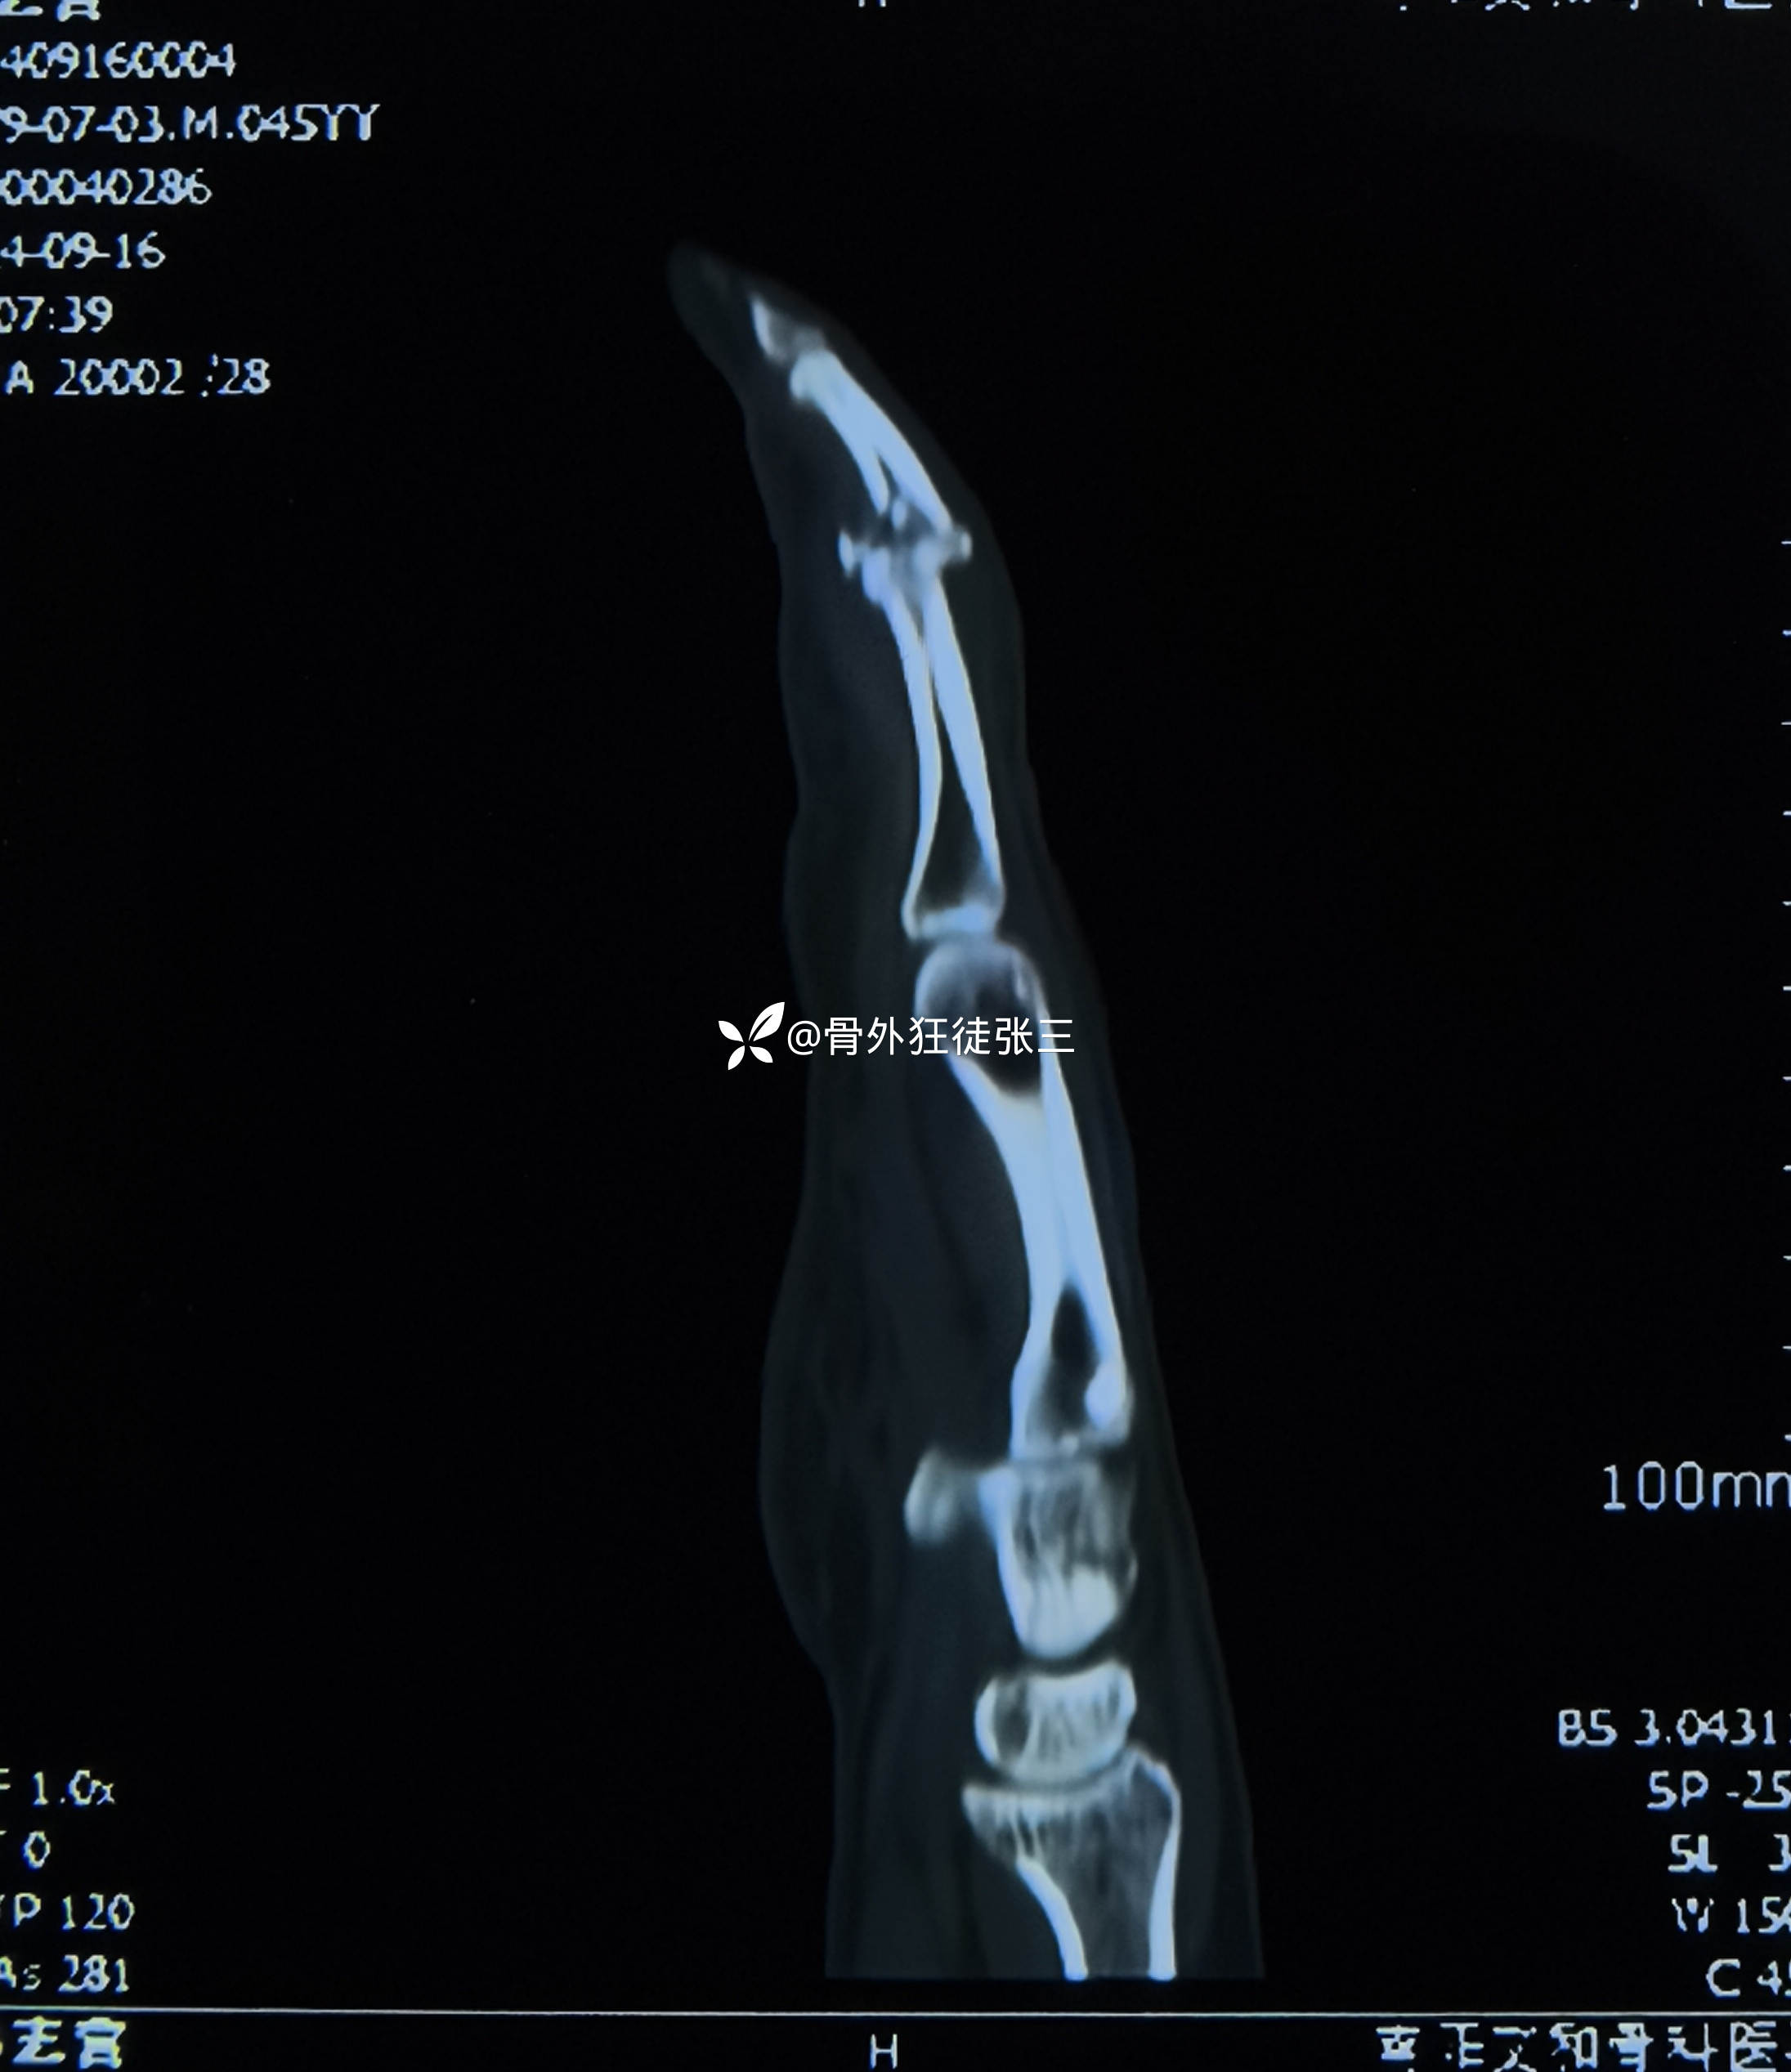

从掌侧in-out-in穿出

折弯阻挡骨块

透视发现骨块无法复位

脱位无法纠正

先复位脱位,再透视

发现关节不稳无法维持复位

只能克氏针固定关节

保持复位

再次用阻挡克氏针复位骨块

透视发现骨块复位

关节复位